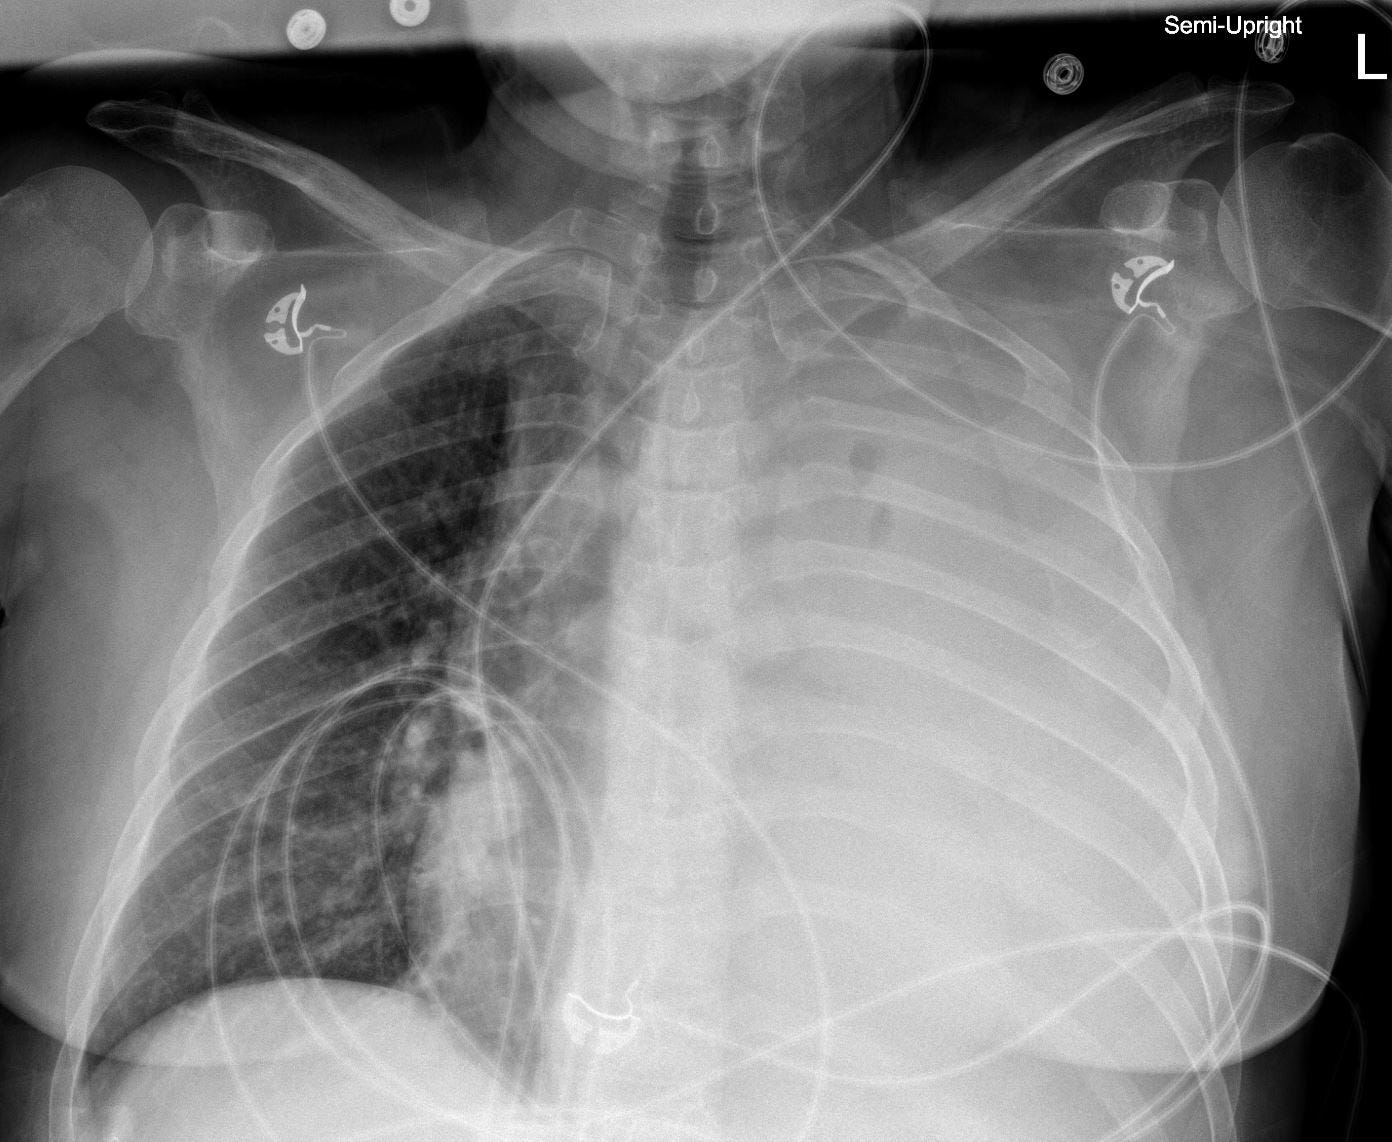

Chest film (4 days prior):

He was electively intubated, and a chest tube was placed with 2 liters of straw-colored fluid evacuated immediately.

The pleural fluid had an LDH of 80 U/L (serum: 220), protein 1.2 g/dL (protein: 4.2), culture-negative, with 120 polymorphonucleocytes per μL.